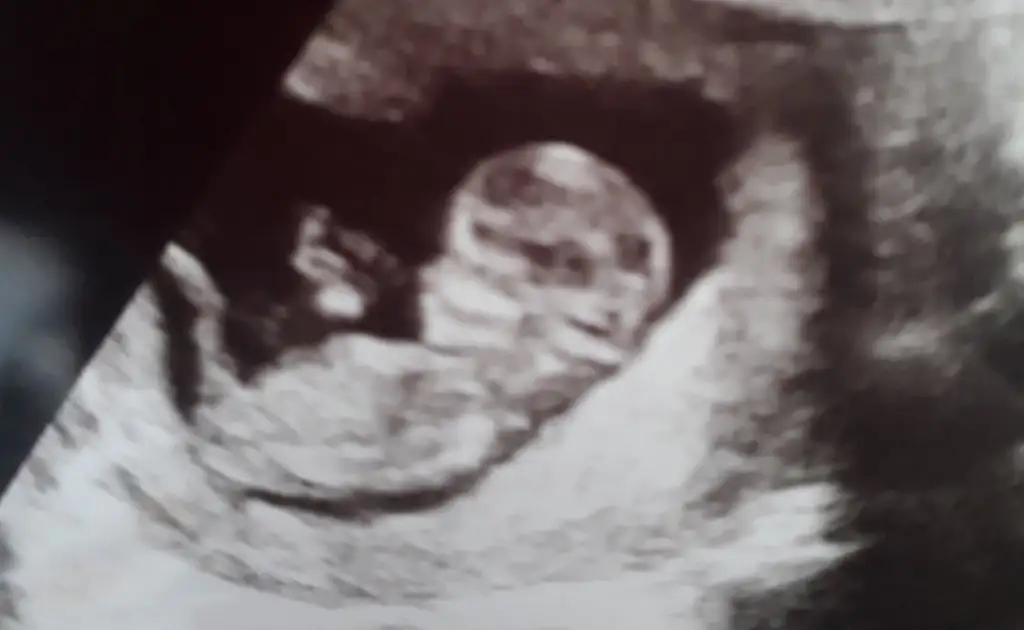

Merhaba bana da tahmin yapabilir misiniz 12+1 günlük Ikra meyra Ikra meyra

• DD19450C-941F-4568-B972-8C1806F513D4.webp

DD19450C-941F-4568-B972-8C1806F513D4.webp

• C649B114-111B-4B98-8592-EBD54A7C3022.webp

C649B114-111B-4B98-8592-EBD54A7C3022.webp

• 83B9F7EE-030B-4BF5-9045-9764601044CB.webp

83B9F7EE-030B-4BF5-9045-9764601044CB.webp

18,6 KB · Görüntüleme: 92